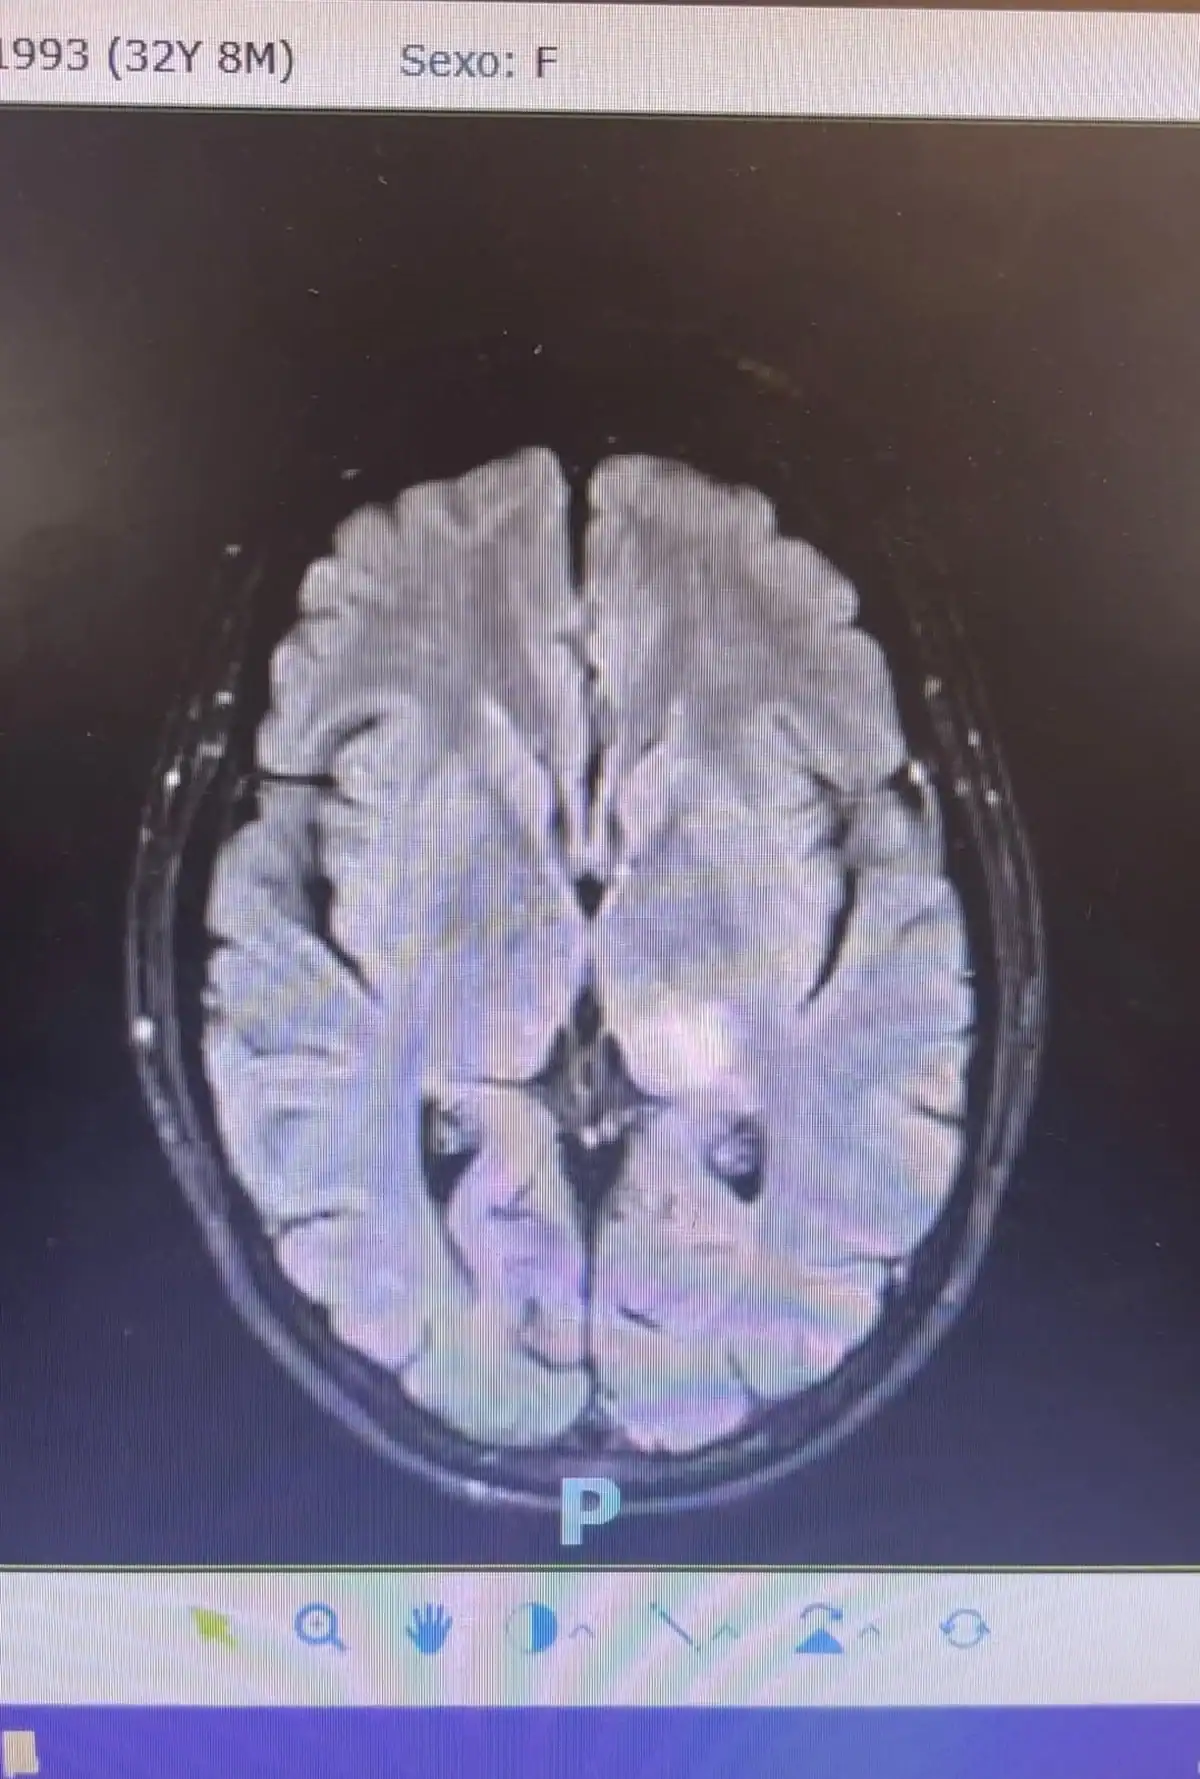

Daniella forneceu mais detalhes: “Na última ressonância de crânio, detectamos uma possível vasculite. Vasco = vaso / Lite = inflamação, ou seja, uma inflamação dos vasos. No meu caso, foi identificado em apenas um, na cabeça”, contou, antes de acrescentar.

“Desde então, estou fazendo exames para confirmar se essa foi a causa do AVC e se há inflamações em outras partes do corpo: punção lombar, exames de sangue, arteriografia. Fiz de tudo um pouco (risos)”, afirmou.

Logo após, Daniella comentou sobre o diagnóstico: “Por enquanto, só encontramos essa inflamação única no vaso da cabeça e a decisão médica foi tratar com corticoide intravenoso para mitigar os riscos”, pontuou.